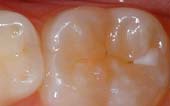

Seal Out Decay

A sealant is a protective coating that is applied to the chewing surfaces (grooves) of the back teeth (premolars and molars), where four out of five cavities in children are found. This sealant acts as a barrier to food, plaque and acid, thus protecting the decay-prone areas of the teeth.

Your pediatric dentist may also recommend protective sealants or home fluoride treatments for your child. Sealants can be applied to your child’s molars to prevent decay on hard to clean surfaces.